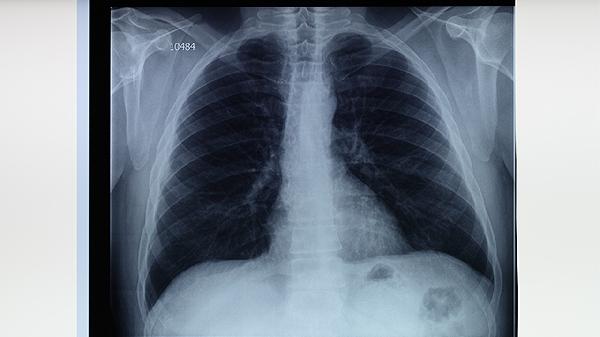

肺结核患者需坚持全程规律用药,不可自行停药或减量。治疗期间应保持高蛋白饮食如鸡蛋、鱼肉,适当补充维生素丰富的新鲜果蔬。注意隔离生活用品,咳嗽时掩住口鼻,定期进行痰菌检查和胸部影像学复查。出现药物不良反应需及时与主治医生沟通调整方案,忌烟酒及辛辣刺激食物以免加重肺部损伤。